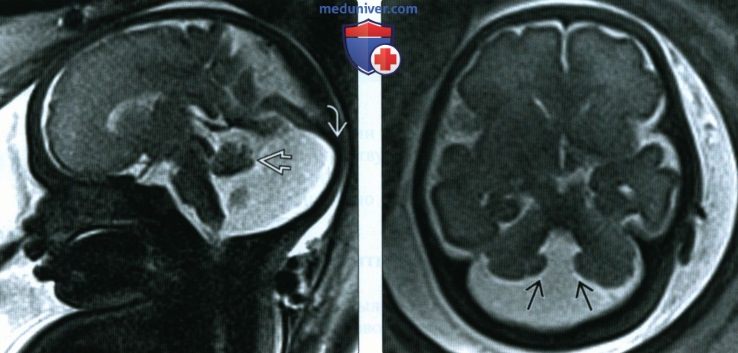

МРТ снимки мальформации Денди-Уокера